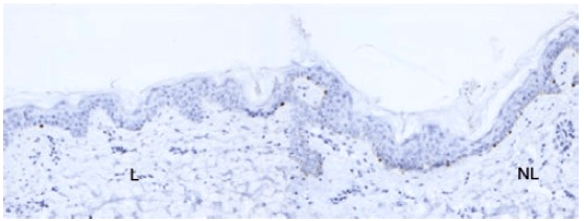

Un autre effet indésirable cutané fréquent est le vitiligo [Figure 6]. Il peut s’accompagner d’une dépigmentation des phanères. Il ne se voit que chez des patients atteints d’un mélanome, surtout traités par un anti-PD-1, et il persiste à l’arrêt du traitement. Cette disparition des mélanocytes pourrait s’expliquer par une réponse T cytotoxique contre des épitopes spécifiques qui seraient partagés par la peau normale et par le mélanome (comme MART-1, GP100, tyrosinase…). Plusieurs études rapportent que son apparition est corrélée à une réponse objective et à une survie globale prolongée ce qui pourrait en faire un marqueur indirect de réponse thérapeutique 11-16.

[Figure 6]

Exemple de vitiligo.

Immunomarquage vitiligo-MART1 dans la peau lésionnelle (L) montrant une diminution des mélanocytes à la jonction dermo-épidermique comparé à l’immunomarquage MART1 de la peau non lésionnelle (NL)